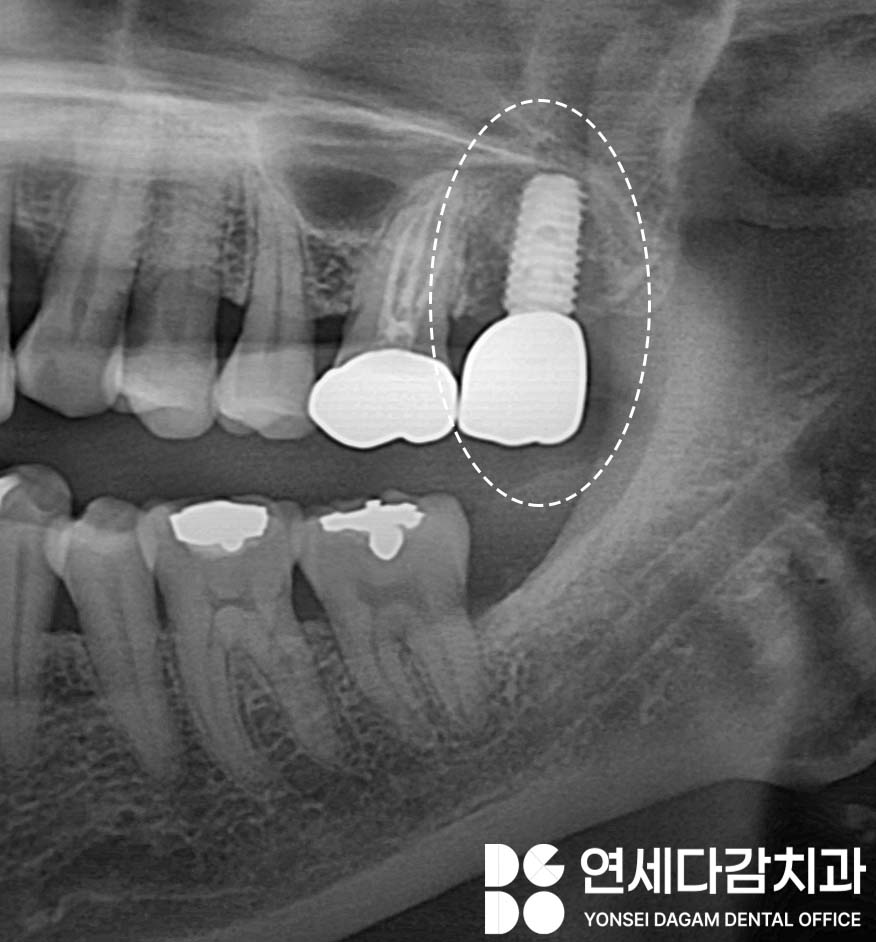

수면 진정 치료를 통한

임플란트 식립이 완료된 후에는

이러한 마취 시스템 덕분에

수술이라는 부담감을 덜어내면

보철을 완성시키는 과정은

더욱 수월하게 됩니다.